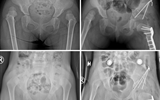

兰大二院采用改良微创Pemberton截骨术个性化治疗两例发育性髋关节脱位患儿